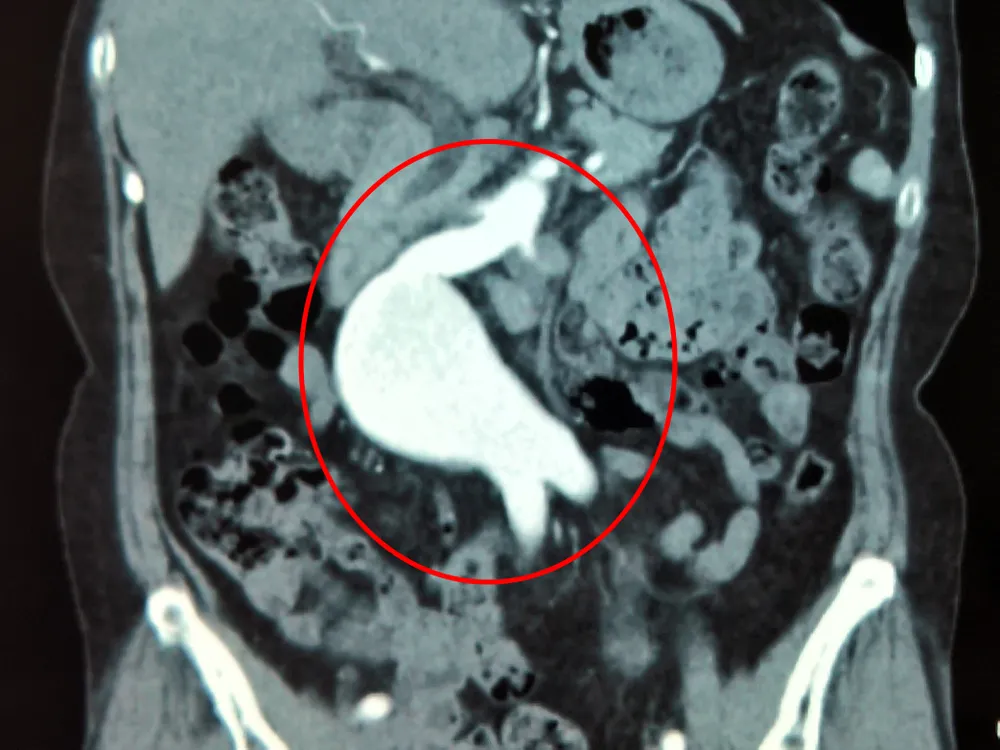

Thay động mạch chủ phình to có nguy cơ vỡ cho bệnh nhân  ảnh 1 Ảnh cắt lát vi tính (CT) - động mạch chủ bụng bị phình to

Tại đây, qua thăm khám lâm sàng kỹ lưỡng và kết quả MSCT160 lát cắt dựng 3D vùng bụng cho thấy bệnh nhân có khối phình động mạch chủ bụng rất lớn, đường kính lên đến 60x70mm.

Khối phình kéo dài ngay dưới hai động mạch thận cho đến các động mạch chậu chung. Do khối phình rất lớn, kèm theo bệnh nhân có triệu chứng đau bụng, hình ảnh viêm quanh khối phình rõ, nên bệnh nhân được chỉ định mổ cấp cứu trì hoãn nhằm tránh nguy cơ vỡ khối phình đe dọa đến tính mạng.